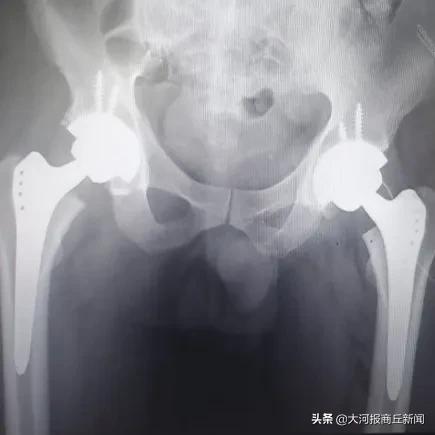

3月2日下午,豫东名医、骨科专家殷晓东院长领衔的柘城县中医院骨科团队在短短三个小时内完成四台人工膝、髋关节置换,其中包含一例高难度高龄患者双髋关节置换,非常时期下骨科团队丰富的经验和精准的操作技术再显不凡身手,较平均用时节约了一半时间,是柘城中医院开展关节置换技术多年来再次跑出的中医院新速度。

▲精技术,强疗效——关节置换重塑健康人生

近年来,柘城中医院骨科一直致力于引进国内外各项先进技术,用于治疗骨关节疾病。在治疗股骨头坏死、膝关节骨性关节炎以及腰间盘突出症等疾病方面形成了独特的三阶梯式治疗方法。术后第二天即可下床走路,快速康复重建关节功能,截止目前,已成功完成了多例多关节同时置换及数十例百岁老人置换病例,受到了患者们的广泛赞誉。